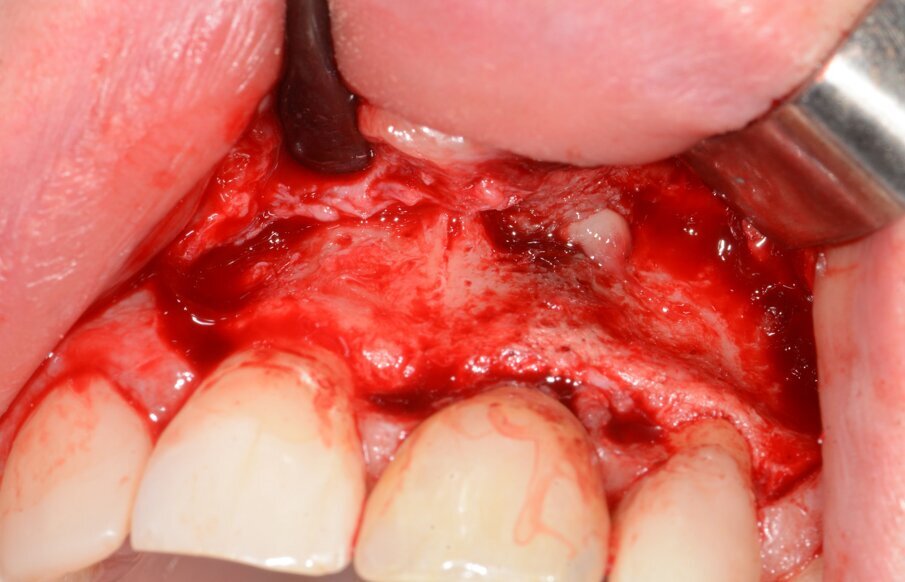

Fig. 9: Granulation tissue visible after flap elevation.

Fig. 10: Granulation tissue removal with Er:YAG laser.

Fig. 16: Granulation tissue removal with Er:YAG.